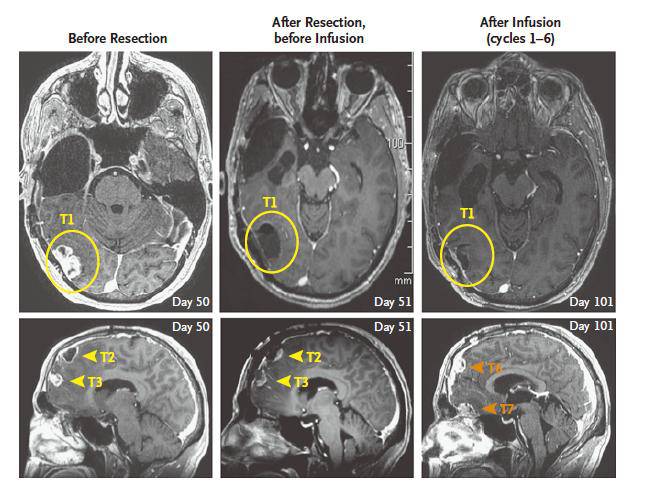

首先,手术切除右侧颞叶、枕叶(T1)以及右侧额叶(T2-T7)的大部分复发肿瘤,再通过导管连续输入免疫T细胞至右侧颞叶和枕叶(T1)的瘤腔内。经过6周期治疗后,该局部肿瘤未见明显复发,而右侧额叶(T2-T7)处肿瘤复发(图1)。与此同时,患者出现下肢麻痹;全脊髓MRI发现肿瘤脊柱椎管转移,其中2处脊髓肿瘤直径为18mm和4mm。此后,改变给药途径,由局部给药改为脑室内系统性给药,将免疫T细胞持续注入患者右侧脑室,共进行10个周期。至治疗的第133天,发现颅内和脊髓内所有肿瘤均缩小;治疗的第190天时缩小达77%;再继续该治疗至MRI或PET-CT检查中无法辨认颅内和脊髓的转移性肿瘤(图2)。与此同时,内源性免疫细胞和炎症因子,包括IFN-γ、TNF-α、IL-2、IL-10和CXCL9等,迅速增加。治疗持续7.5个月,肿瘤无进展,提示通过脑室给靶向IL13Rα2药物的CAR-T疗法是一项有效的治疗措施。但治疗后第228天,在与原肿瘤不相邻的、甚至远隔处出现新发病灶。

图1. 右侧颞叶、枕叶的T1处复发GBM部分切除后瘤腔内给以输入免疫T细胞治疗,发现T1局部未见肿瘤明显进展,而右额叶T2-T7处的肿瘤增大。